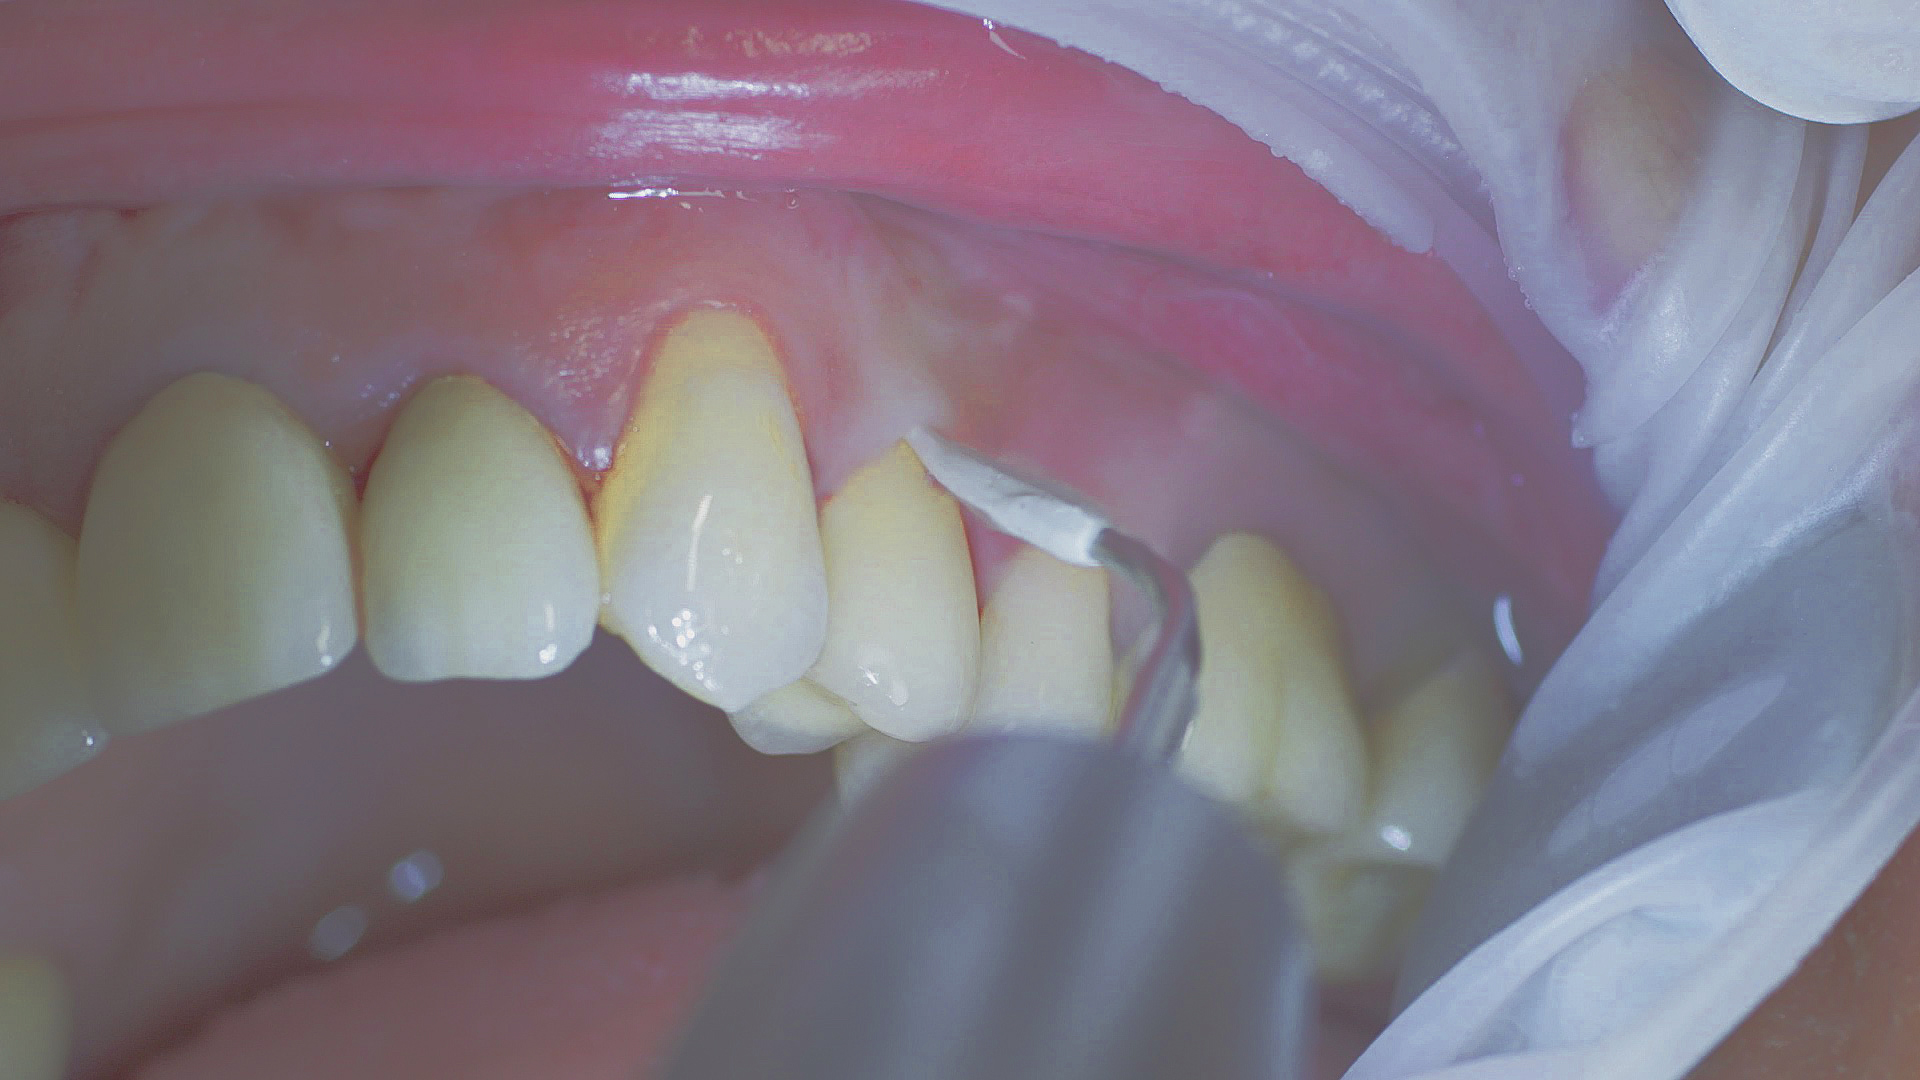

Healthy peri-implant tissue does not show any signs of redness, swelling or bleeding, neither does it secrete pus when probed.[5] Based on the consensus document, Prof. Giovanni Salvi explained the importance of regu- lar probing — preferably with a flexible probe, as implant components often tend to obstruct the procedure.[5] In the case of mucositis or initial peri-implantitis already being present, the non-surgical removal of hard deposits and biofilm should be attempted first. For this purpose, ultra- sonic power and special instruments designed to protect the implant should be employed (Fig. 3; piezo scaler Tigon+ with 1I, W&H). In case of no remission, the recall frequency needs to be increased. However, specific recommendations, applicable to individual cases, are not yet available in this context.[15]

Fig. 3: Implants and superstructures can be successfully cleaned with ultrasonic devices and special plastic instruments during postoperative care or non-surgical therapy.